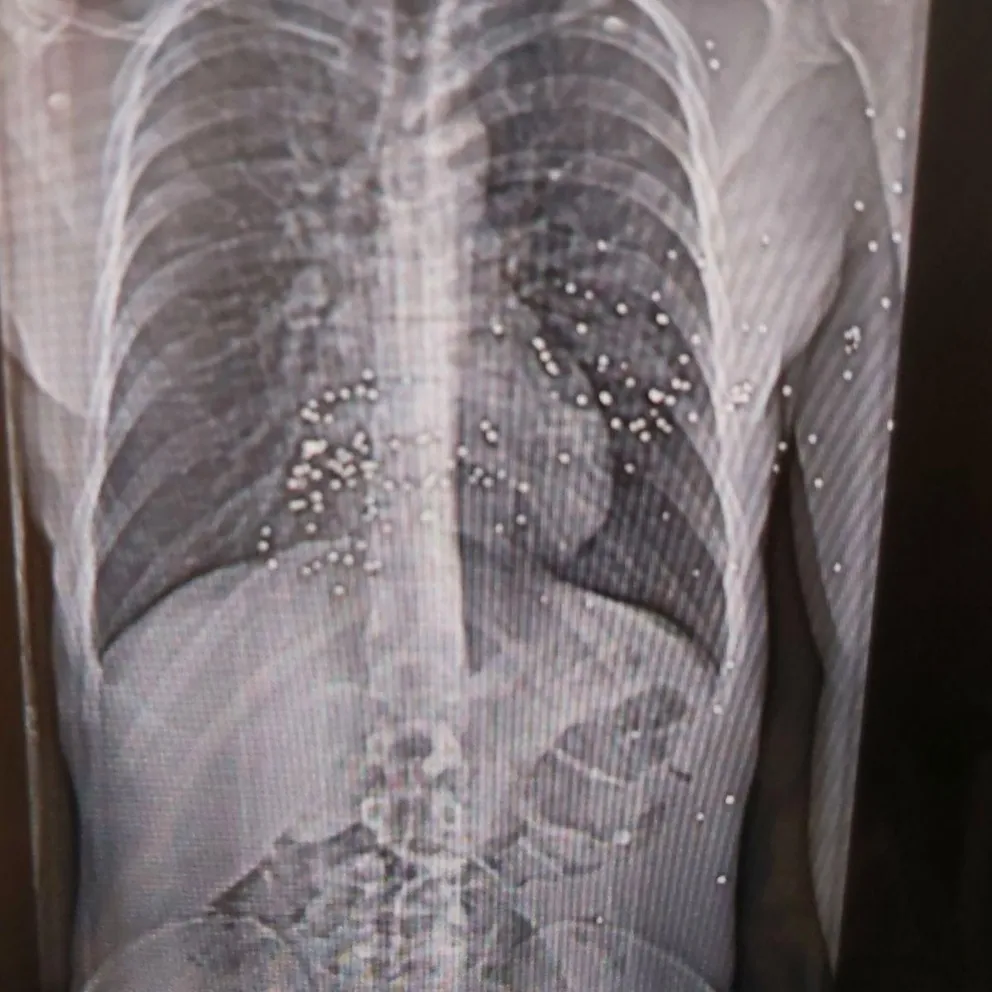

نیویورکر نوشت اعضای کادر درمان در هفتههای اخیر خود به مستندسازی شواهد حملات حکومتبه مردم ایران پرداختهاند و برخی مدارک از جمله تصاویر سیتیاسکن مجروحان را در اختیار این مجله قرار دادهاند.

نرگس این وضعیت را «جهنمی» توصیف کرد: نوجوانی ۱۴ ساله با پاهایی نحیف که با ساچمههای فلزی هدف قرار گرفته بود؛ مردی با حفرهای به اندازه توپ تنیس در ساق پا که او در بخیه زدن آن کمک کرد.